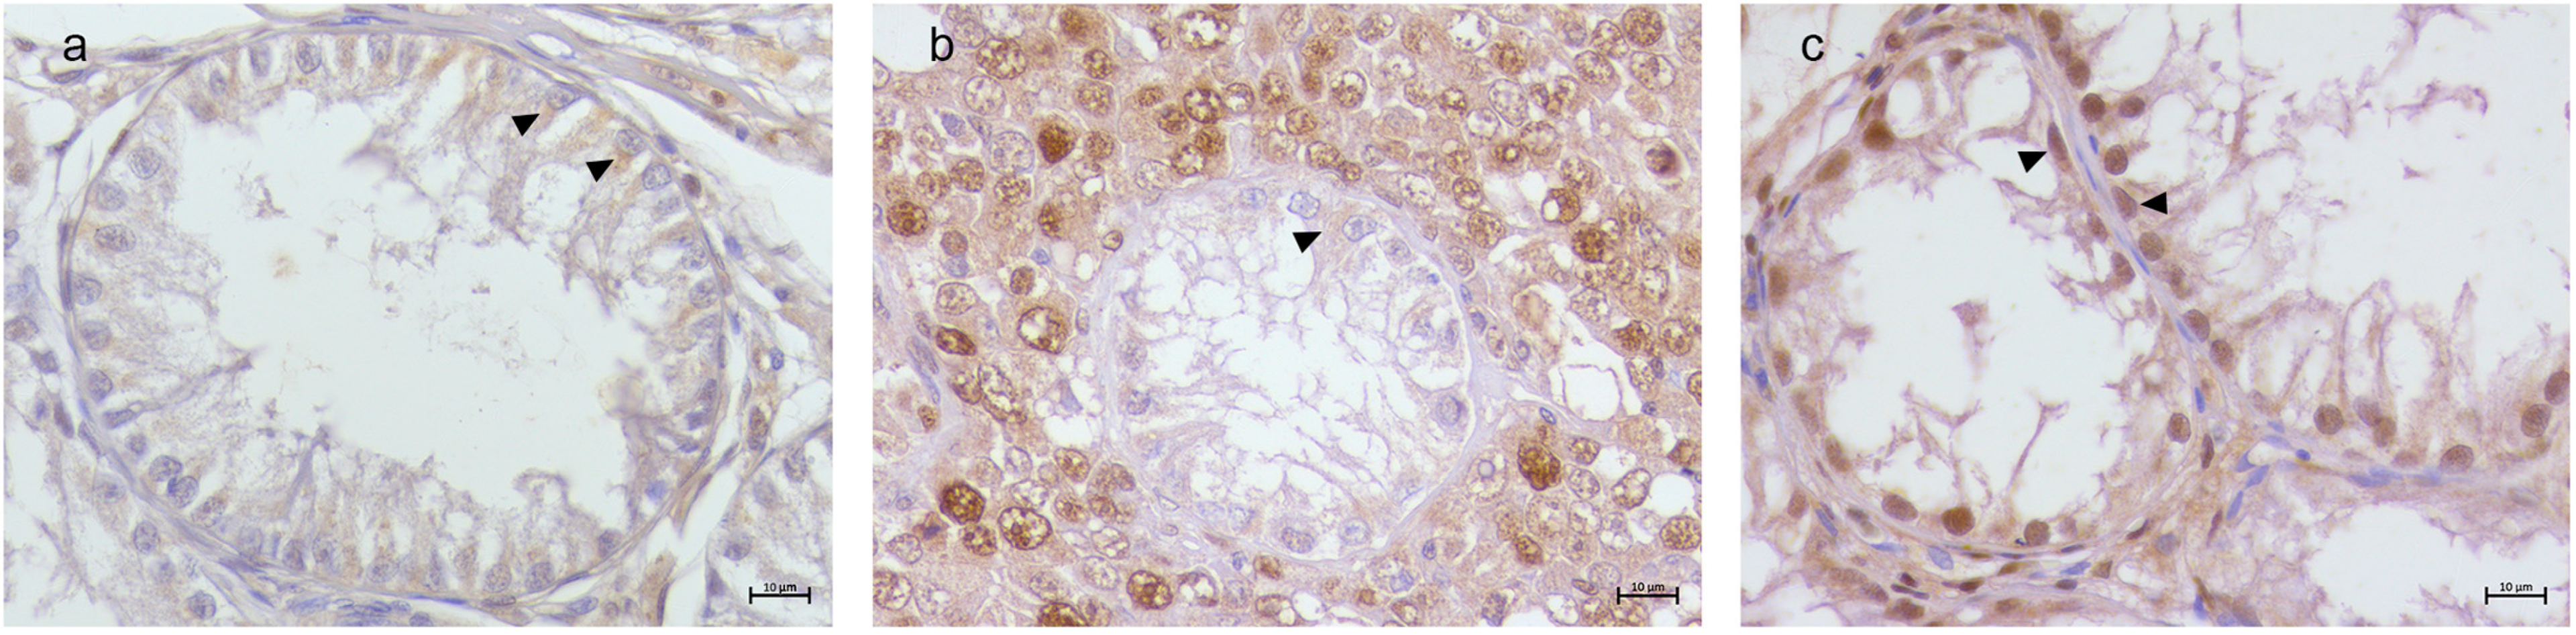

3.2. Immunohistochemical Results